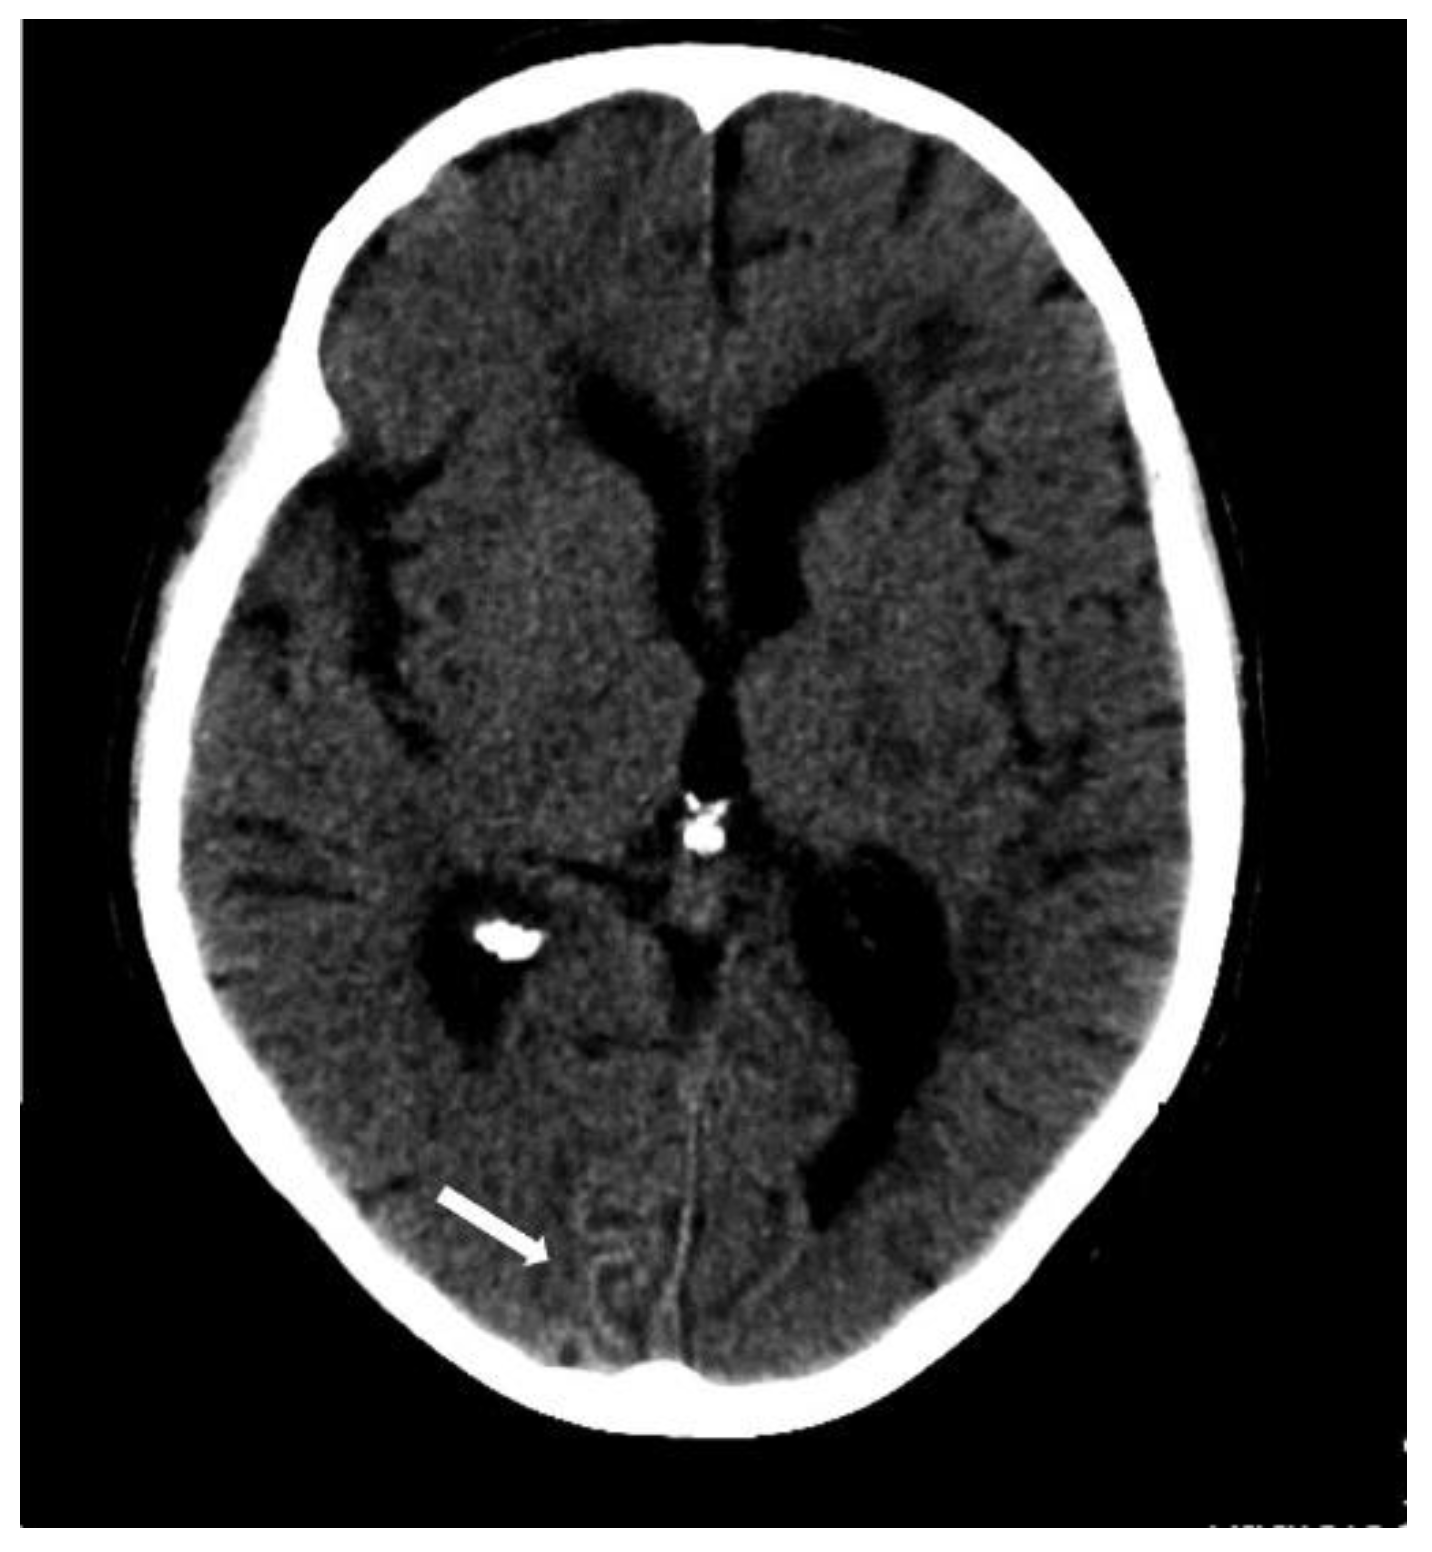

5.1.1. Lobar Hemorrhages

5.1.3. Convexity Subarachnoid Hemorrhage

6.2. Subarachnoid Extension of Lobar Hemorrhage